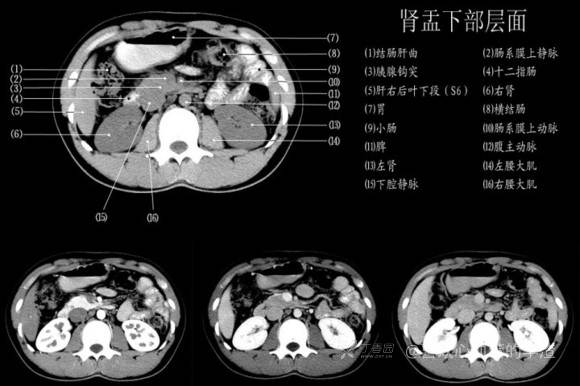

其实你离掌握上腹部 CT 影像只有一套高清实用图谱的距离,下面把我最喜欢的这本图谱分享给大家,为了方便阅读,我加了中文标识。后面附赠几张血管相对位置解剖关系图片,帮助大家理解(文中多图,建议在 wifi 环境下查看)。